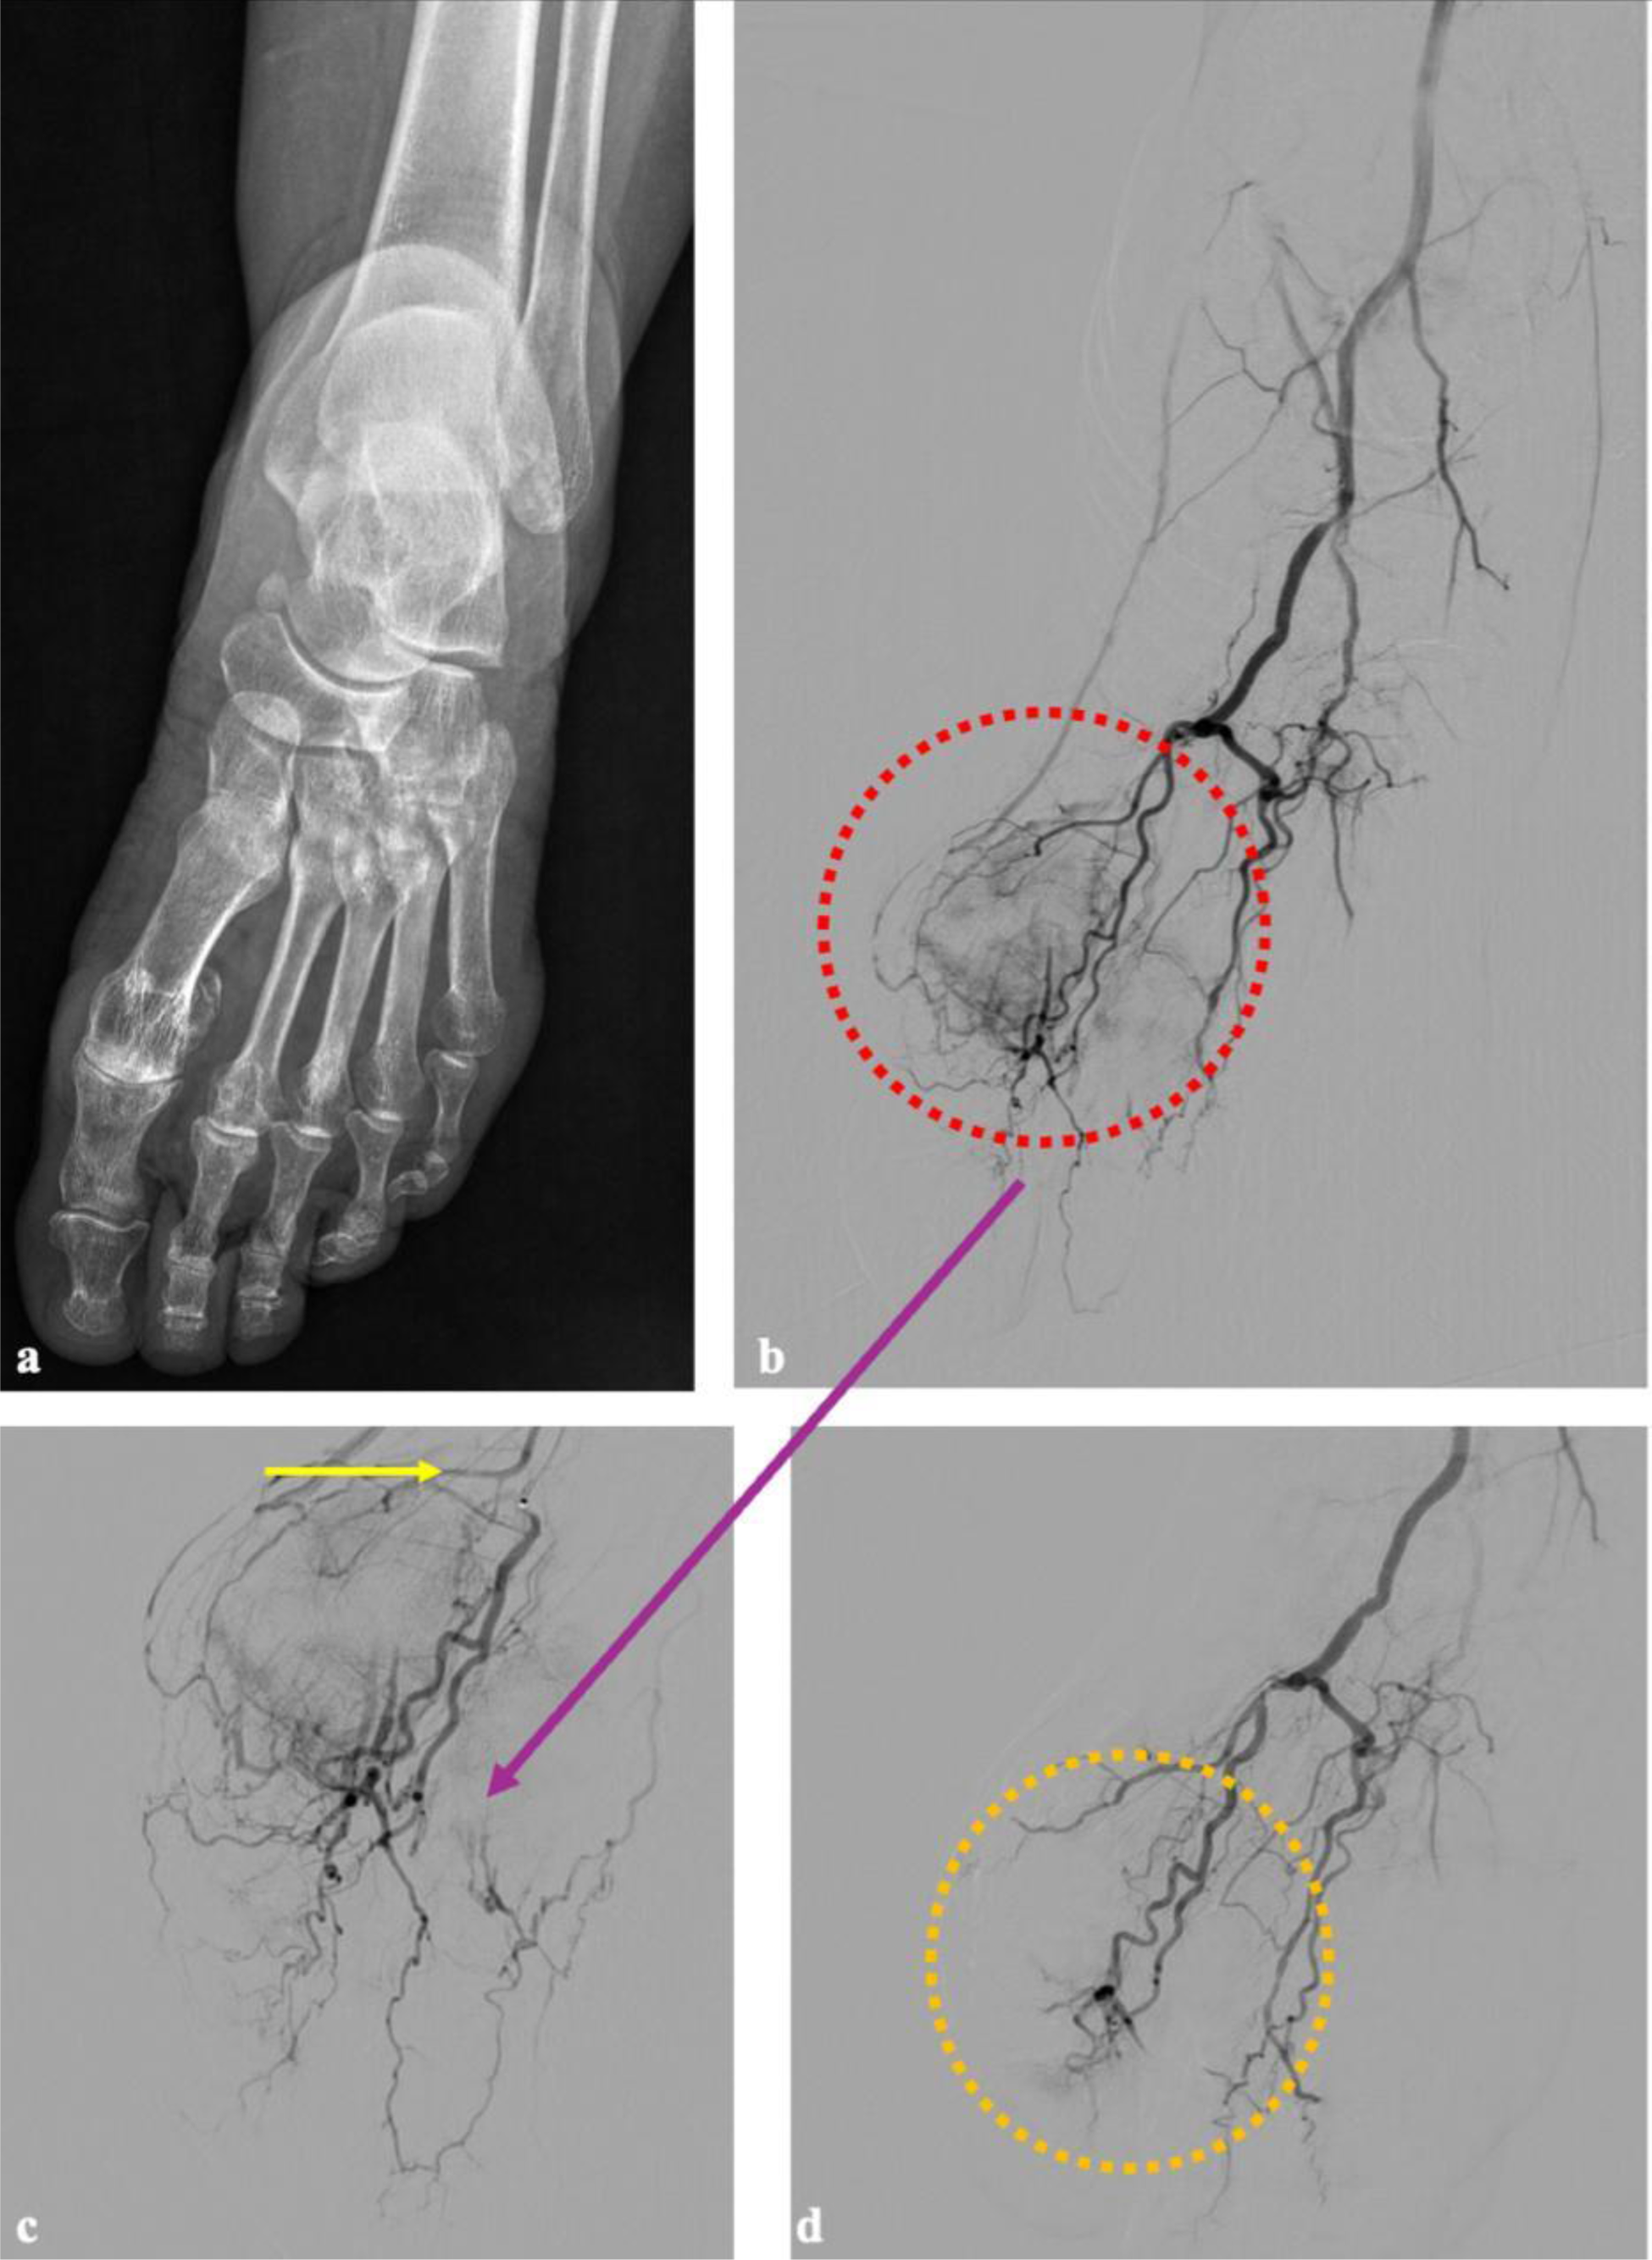

Methods: Patients with chronic MTPJ pain with diverse etiologies were enrolled. Pre-procedural radiographs assessed bony structures, joint space narrowing, and signs of osteoarthritis (Figure 1a and 2a). Following local anesthesia with 2% prilocaine, vascular access was established using the Seldinger technique via the common femoral artery with 4F vascular sheath in antegrade approach. Prior to imaging, patients received 3000 IU of heparin sodium. The procedure began with roadmap imaging using a 0.035-inch hydrophilic soft guidewire and a 4F vertebral catheter to access the anterior tibial artery through the popliteal artery. Angiographic imaging identified hypervascularity in the first MTPJ, and superselective catheterization of the dorsal metatarsophalangeal artery was achieved using a 1.8 F microcatheter and a 0.014-inch guidewire. Embolization was performed using an imipenem/cilastatin suspension, administered in incremental doses of 0.5 mL until hypervascular blush resolved, while preserving distal vascular patency. Steps of the procedure were demonstrated in Figure 1b-c-d and 2b-c-d. Hemostasis was achieved by manual compression of the femoral puncture site for 15 minutes, and patients were observed in the recovery unit for six hours. All patients were discharged on the same day in the absence of complications. Clinical parameters, including Visual Analog Scale (VAS) scores, functional disability, and weekly analgesic use, were documented pre-procedure and at 4 weeks post-procedure.

Preporcedure radiographic and procedural angiographic images of a patient with right foot embolization. In image (a) a plain radiograph image of the patient with underlying seronegative rheumatoid arthritis and narrowing in both metatarsophalangeal and tarsometatarsal joints suggesting secondary osteoarthritis is given. The first procedure image (b) represents a subtracted DSA view of the entire right foot, obtained by injecting contrast through the A. dorsalis pedis via macrocatheteraziation. The image (c) is the appearance of the first dorsal metatarsophalangeal artery after superselectively catheterizaiton using a microcatheter (c), the resulting an image demonstrating a more prominent vascular blush and increased visualization of venous structures. In image (d), following superselective catheterization and embolization with imipenem/cilastatin, macrocathetarization image shows the vascularization of the entire foot and disappearance of the blush with the while preservation of distal vascular structures.